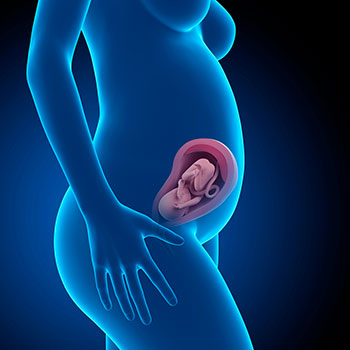

Parabéns, chegada à 27ª semana de gravidez, chegas também ao terceiro trimestre de gravidez! O teu bebé pesa cerca de um kilo e mede cerca de 36 centímetros.

Grávida de 27 semanas

Idade do feto: 25 semanas.